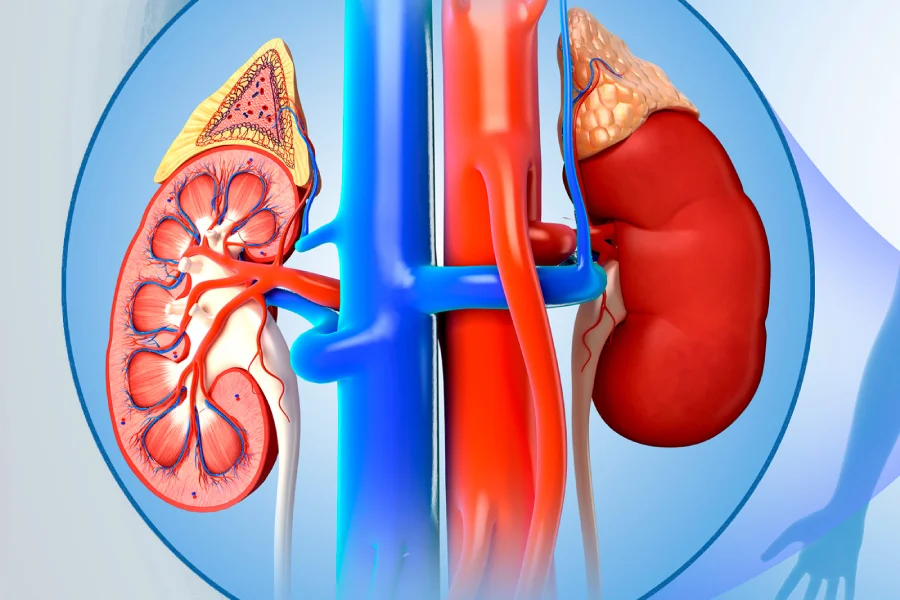

PUJ obstruction, also known as Pelvi-Ureteric Junction obstruction, is a condition where there is a blockage at the junction between the kidney (renal pelvis) and the ureter (the tube that carries urine to the bladder). This blockage prevents normal urine flow, leading to swelling of the kidney, a condition called hydronephrosis.

PUJ obstruction may occur due to:

Narrowing at the junction between the kidney and ureter

Abnormal muscle development at the junction

Crossing blood vessels compressing the ureter

Pyeloplasty is the standard surgical procedure and involves:

Removing the narrowed segment

Reconnecting the healthy ureter to the kidney

Restoring normal urine flow